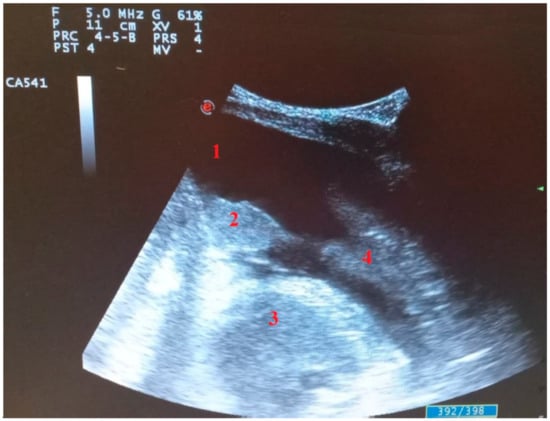

- Di Serafino, M.; Notaro, M.; Rea, G.; Iacobellis, F.; Paoli, V.D.; Acampora, C.; Ianniello, S.; Brunese, L.; Romano, L.; Vallone, G. The lung ultrasound: Facts or artifacts? In the era of COVID-19 outbreak. Radiol. Med. 2020, 125, 738–753. [Google Scholar] [CrossRef] [PubMed]